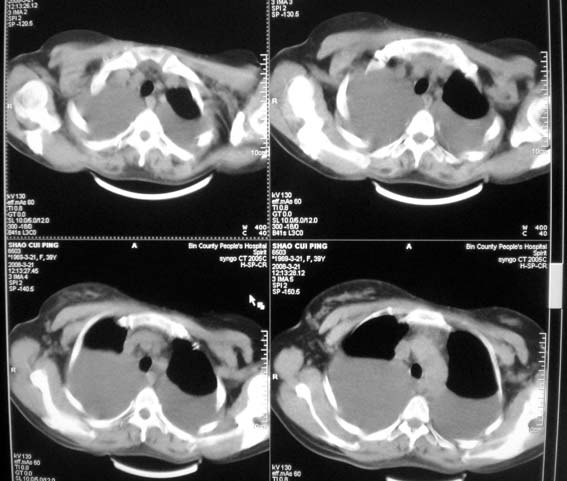

以下是引用卜一在2008-3-22 1:48:00的发言:[br][br] [br] 大量胸腔积液伴肺组织膨胀不全+心包积液。建议行纤支镜! [br] [br]

以下是引用随光逐影在2008-3-21 23:13:00的发言:[br]1)右肺中叶及左肺上叶舌段感染性病变。2)右肺中叶周围型肺癌待排。3)双侧胸腔积液并双下肺部分肺组织膨胀不全。4)心包积液。

以下是引用拾荒者在2008-3-22 21:21:00的发言:[br]胸腔积液、心包积液,双下肺膨胀不全,建议穿刺细胞学检查或抽液后进一步ct检查。